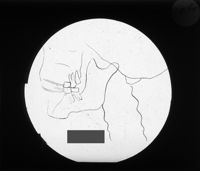

Image[Plaque de projection de radiographies maxillaires.]